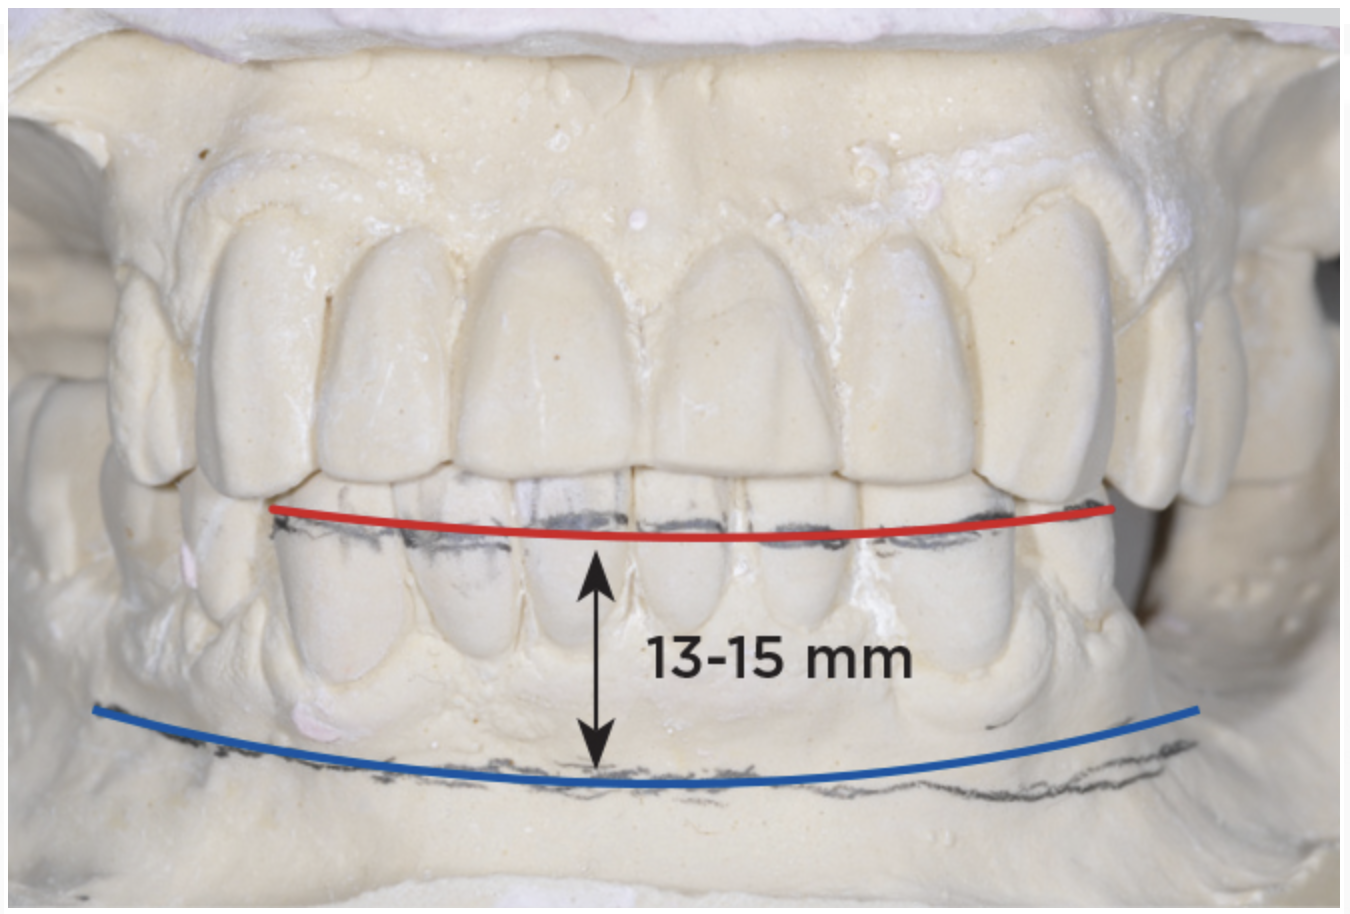

An important advantage of this approach is the ability to simulate bone reduction on the models and verify the presence of 15 mm to 17 mm and 13 mm to 15 mm of required inter-occlusal space for maxillary and mandibular restorations, respectively. This creates a platform for a diagnostic wax-up of the proposed dental rehabilitation and fabrication of wax prosthesis try-ins when necessary. Finally, a modified All-on-4 provisional prosthesis surgical and restorative guide developed by the authors for restoration-driven surgery and simplified restorative procedures is fabricated (Figure 2 through Figure 8).

Fig 5. Bone reduction model surgery performed in mandibular arch to create 13 mm to 15 mm of inter-occlusal space required for the mandibular All-on-4 provisional restoration.

Figure 5